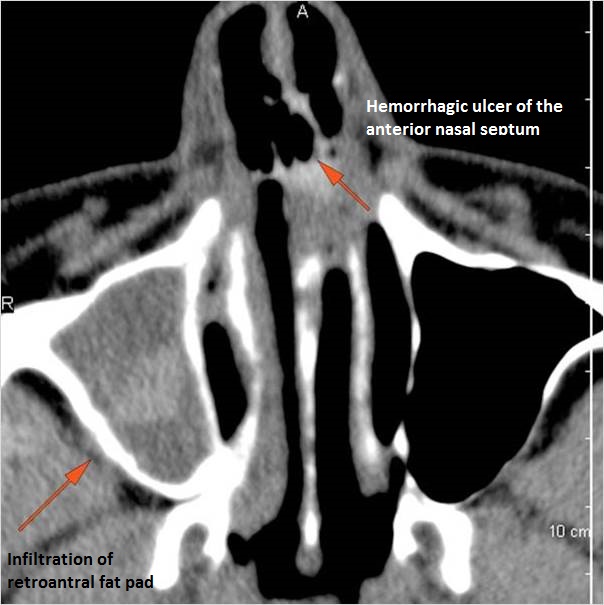

There is focal area of mucoperiosteal thickening or a destructive, ulcerative or necrotic abnormality of the nasal septum turbinates or lateral walls of the nasal cavity. [Yes/No]

The fat pad posterior to the maxillary sinus and within the pterygopalatine fossa are infiltrated. [Yes/No]